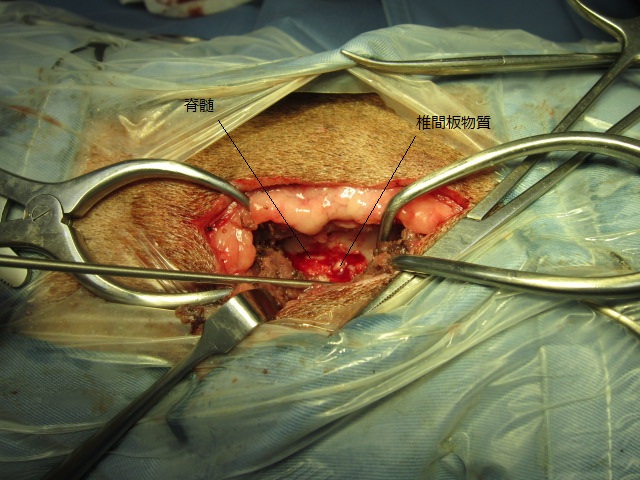

除去した椎間板物質です。

神経症状を早期に回復するためには、できるだけ早く圧迫物質を取り除くことが必要です。